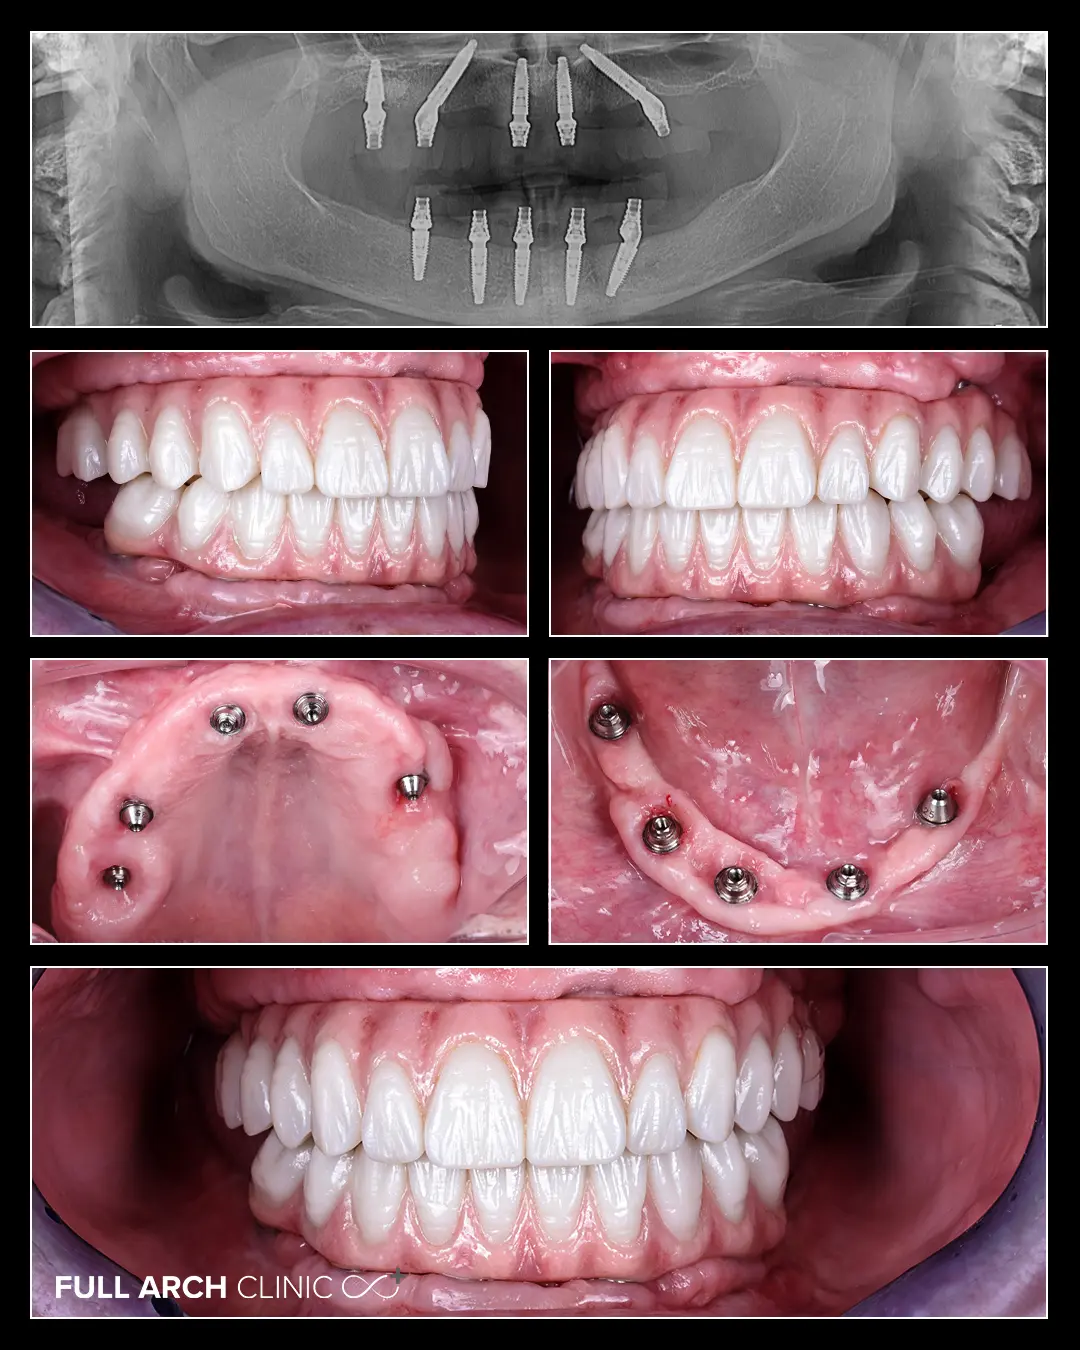

La prima consultație, aveam o lucrare veche sus, o proteză parțială jos și câțiva dinți mobili. Nu știam exact diagnosticul – nimeni nu îmi spusese clar că am parodontoză. Aveam și câteva implanturi puse cu ani în urmă, dar pe care nu fusese realizată nicio lucrare. Domnul doctor mi-a explicat calm și logic că, pentru a reconstrui totul corect și pe termen lung, trebuie făcută „curățenie”: extracții, îndepărtarea infecțiilor, repoziționarea corectă a planului de tratament.

Când am trecut la lucrarea finală, diferența a fost de la cer la pământ. Sunt atât de frumoși, naturali și perfecți încât nici în tinerețe nu am avut asemenea dinți. Am ales nuanța B1, alb natural. Familia mi-a spus că par dinții mei, doar că mai frumoși. Și așa simt și eu.